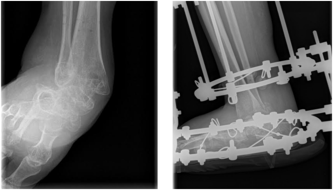

W ubiegły poniedziałek 19 czerwca b.r. w poznańskiej klinice Janusz przeszedł trudną i skomplikowaną operację naprawczą prawej stopy, ratując ją przed amputacją.

„Podczas operacji dr Stawicki przywrócił oś do prawidłowej pozycji, nastawił zwichniętą kość piętową, na której chodziłem tyle czasu, a także co się później okazało - musiał usunąć pozostawione wolne fragmenty kości, które się nie zrosły. Stopa jest ustabilizowana dwoma śrubami oraz kilkoma implantami metalowymi - bolcami, kotwicami i innymi "wynalazkami". Zabieg trwał ponad 3 godz. (niecałe 4 godz. z podawaniem znieczulenia, przewiezieniem na salę itp.) i zdaniem dr Stawickiego był jednak trudny i skomplikowany. Ale udany - i to chyba najważniejsze. Prawie cały czas jestem na środkach przeciwbólowych, na drugi dzień ból był okropny. Byłem znieczulony w kręgosłup, więc nie czułem bólu od pasa w dół z nogami, ale byłem cały czas przytomny podczas operacji. Słyszałem wszystko - odgłosy piły, młotków, jakiegoś stukania i brzęczenia... jak w jakimś warsztacie :-) Mam na nodze plastikowy gips.

Wg doktora Stawickiego udało się osiągnąć zamierzony cel, chociaż ze względu na ryzyko wystąpienia martwicy w okolicach zrośniętych częściowo kości po ostatnim zabiegu na Borowskiej, dr wolał jednak pozostawić taki kształt stopy, odchylonej nieco w prawo, ale całkowicie zmieniła się struktura anatomiczna kości w tej stopie.”